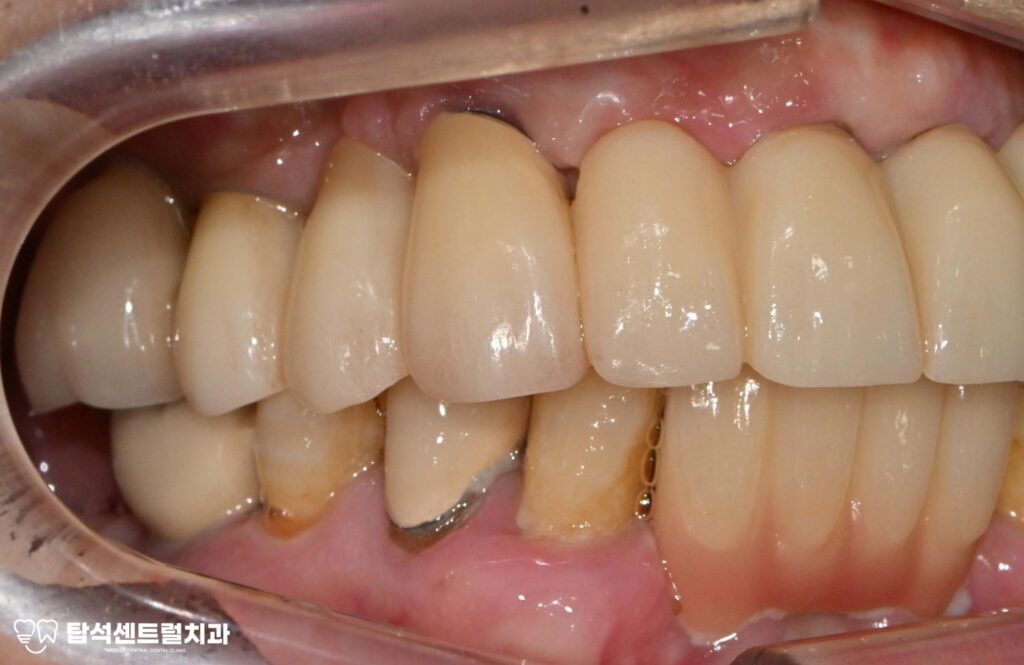

예를 들어 위턱 앞니 부위에 심은

브릿지 형태의 보철을 살펴보면

여러 개의 고정체가 연결되어 있어도

특정 부위에만 골소실이 집중될 수 있습니다.

한쪽은 상태가 양호하더라도 다른 쪽에

임플란트 주위염이 발생하면

해당 부위만 선택적으로 제거하고

새로운 치료 계획을 수립하게 됩니다.